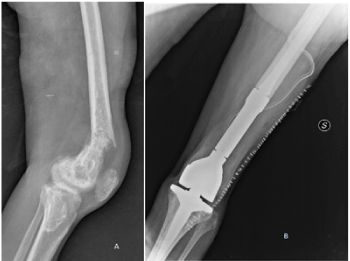

Figure 1. MRI showed multiple bilateral bone infarcts around right and left knee, on the left distal femur necrotic area, heteroplastic tissue grown with rupture of cortices and soft tissue expansion